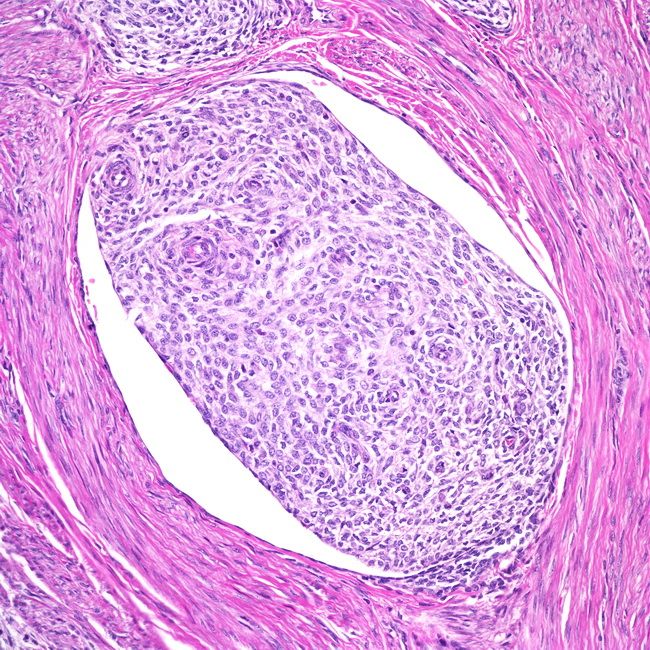

Склероз кисты